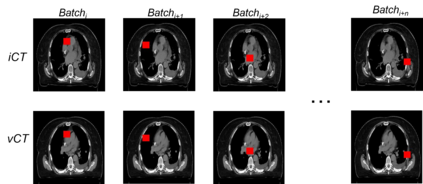

Purpose: In some proton therapy facilities, patient alignment relies on two 2D orthogonal kV images, taken at fixed, oblique angles, as no 3D on-the-bed imaging is available. The visibility of the tumor in kV images is limited since the patient's 3D anatomy is projected onto a 2D plane, especially when the tumor is behind high-density structures such as bones. This can lead to large patient setup errors. A solution is to reconstruct the 3D CT image from the kV images obtained at the treatment isocenter in the treatment position. Methods: An asymmetric autoencoder-like network built with vision-transformer blocks was developed. The data was collected from 1 head and neck patient: 2 orthogonal kV images (1024x1024 voxels), 1 3D CT with padding (512x512x512) acquired from the in-room CT-on-rails before kVs were taken and 2 digitally-reconstructed-radiograph (DRR) images (512x512) based on the CT. We resampled kV images every 8 voxels and DRR and CT every 4 voxels, thus formed a dataset consisting of 262,144 samples, in which the images have a dimension of 128 for each direction. In training, both kV and DRR images were utilized, and the encoder was encouraged to learn the jointed feature map from both kV and DRR images. In testing, only independent kV images were used. The full-size synthetic CT (sCT) was achieved by concatenating the sCTs generated by the model according to their spatial information. The image quality of the synthetic CT (sCT) was evaluated using mean absolute error (MAE) and per-voxel-absolute-CT-number-difference volume histogram (CDVH). Results: The model achieved a speed of 2.1s and a MAE of <40HU. The CDVH showed that <5% of the voxels had a per-voxel-absolute-CT-number-difference larger than 185 HU. Conclusion: A patient-specific vision-transformer-based network was developed and shown to be accurate and efficient to reconstruct 3D CT images from kV images.